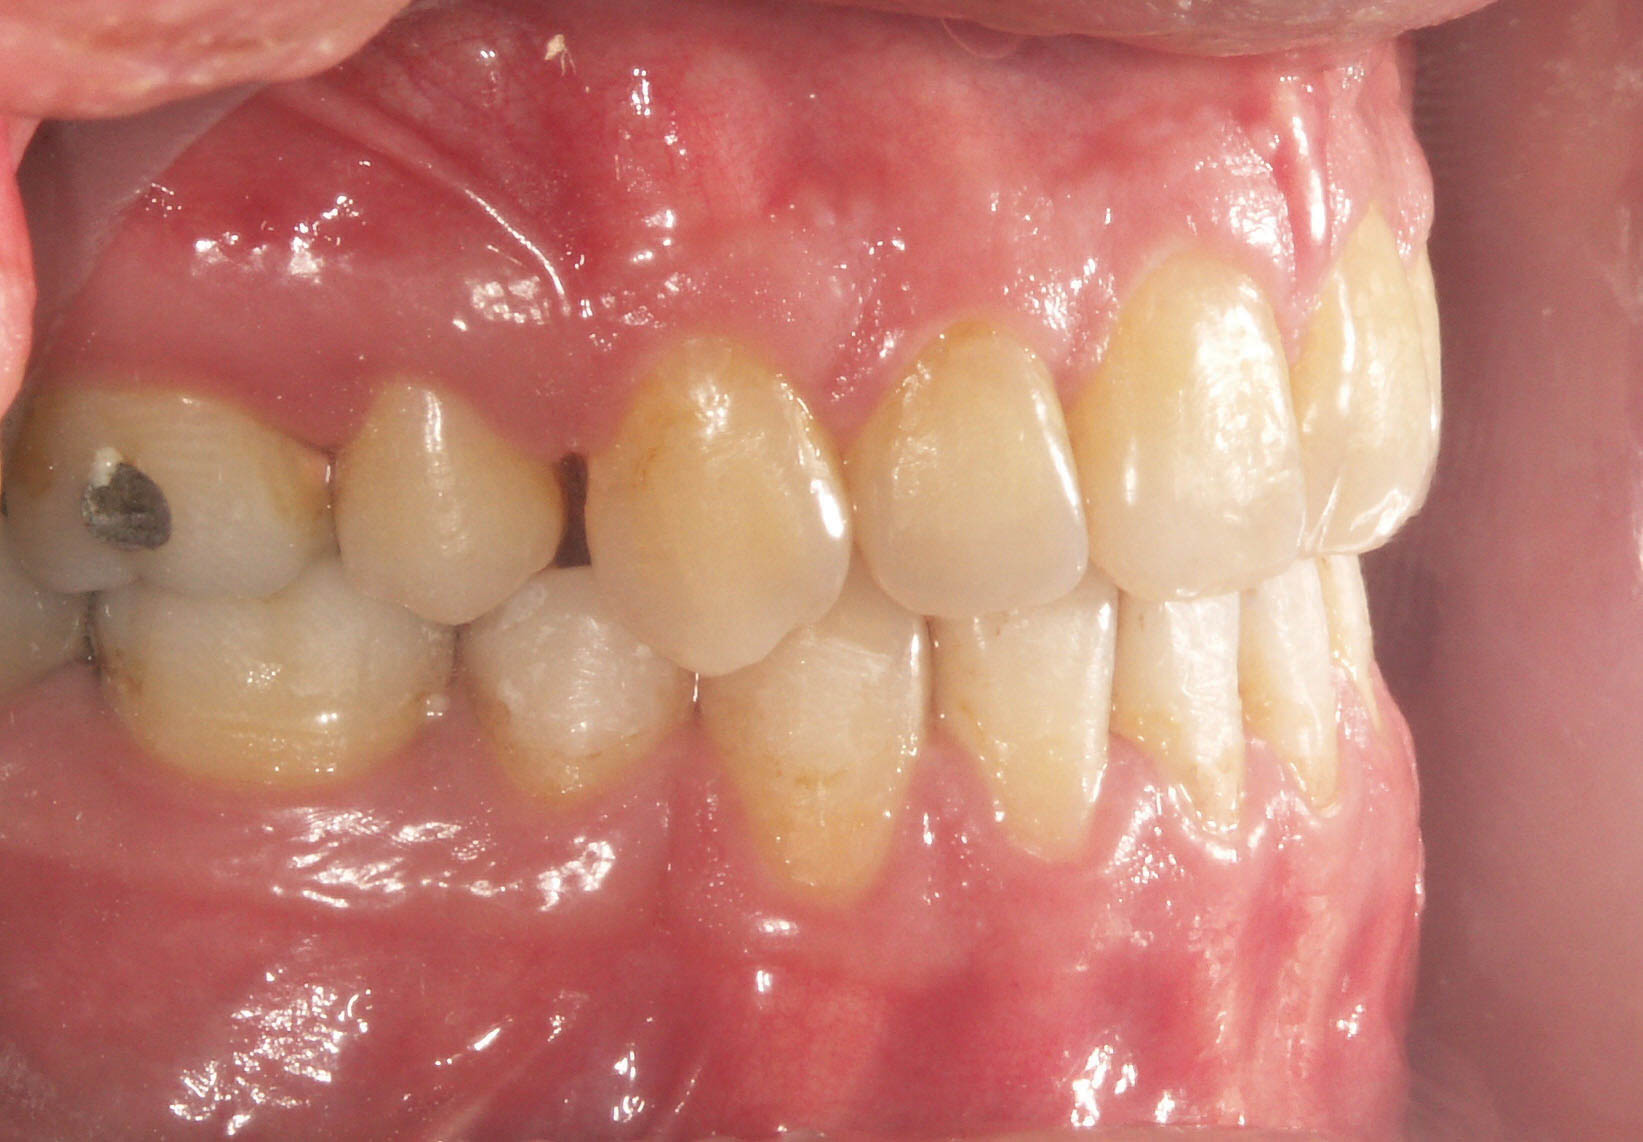

3) در مواردی که ناهنجاری شدید نباشد میتوان دو پرمولر بالا را کشید و قدامیهای بالا را رترود کرد و اورجت بیمار را اصلاح نمود. در این حالت معمولاً پرمولر پائین را نمیکشیم و درمان فک پائین را با استریپ یا حداکثر کشیدن یک انسیزور تمام میکنیم (شکل 23-2 و 24-2). در انتهای درمان این بیماران رابطه مولری یک کاسپ کامل کلاسII تمام میشود (شکل 25-2 و 26-2).

شکل 23-2: در بیمار نیم کاسپ به بالا کلاسII اگر کمبود فضا دو طرف رو هم 6mm-5 باشد میتوانیم یک انسیزور پایین را بکشیم.

شکل 24-2: فضای سانترال کشیده شده برای رفع کمبود فضای دو طرف کافی بود و دندانها در قوس مناسبی قرار گرفتند.